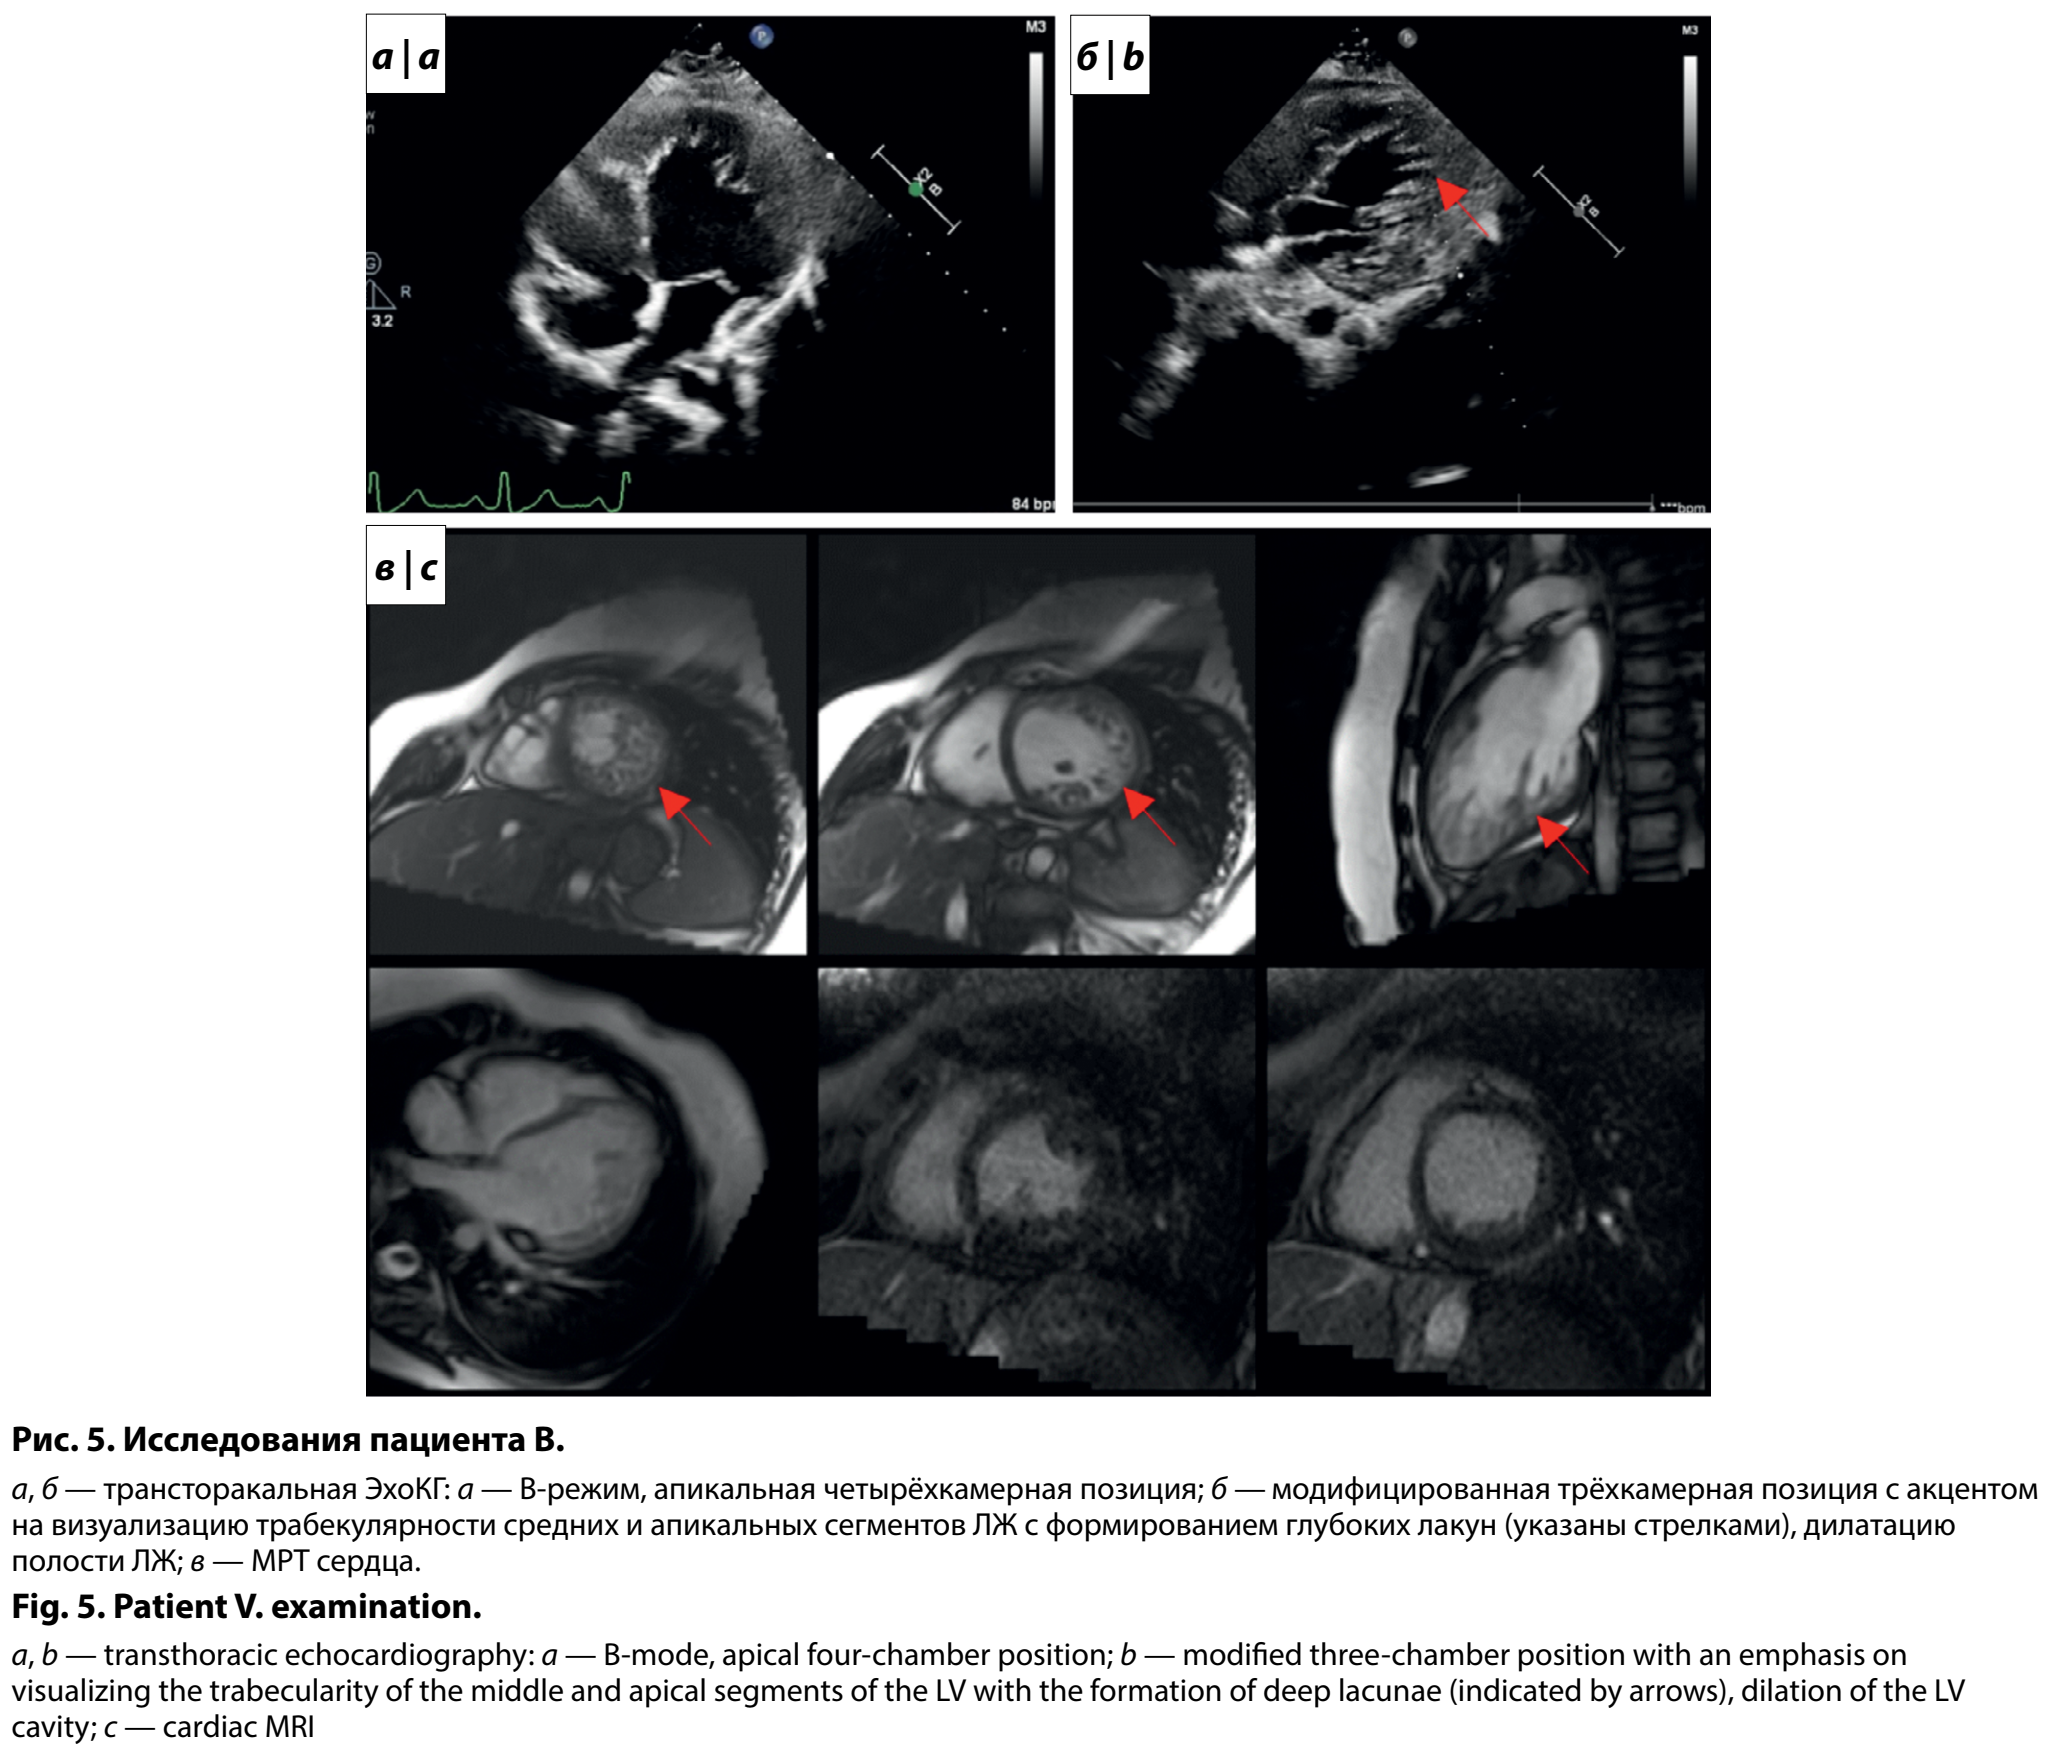

По результатам обследования в кардиологическом отделении Центра в 11 лет отмечен нормальный уровень NTproBNP (12,7 пг/мл). По ЭхоКГ выявлены признаки некомпактного миокарда апикальных и средних сегментов ЛЖ в соотношении 22:6 мм, сферичность полости ЛЖ (индекс сферичности 0,9), пограничный размер полости ЛЖ (Z-score = 2), снижение ФВ по Симпсон до 43%, диастолическая дисфункция по 1-му типу (рис. 5, а, б). По результатам СМ-ЭКГ отмечена склонность к тахикардии, δ-волна в большинстве отведений, значимых нарушений ритма сердца и пауз ритма не регистрировалось. Проведено МРТ сердца (рис. 5, в), подтвердившее некомпактный миокард, снижение функциональных параметров обоих желудочков (ФВ ЛЖ = 39%, правого желудочка — 51%), гипокинез перегородки на всем протяжении, зон фиброза не определялось. Подростку подобрана терапия сердечной недостаточности, продолжено динамическое наблюдение за мальчиком.